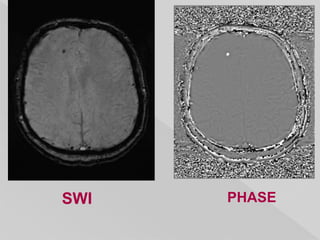

 particularly sensitive to compounds which

distort the local magnetic field and as such

make it useful in detecting blood products,

calcium, etc.

 a 3D high-spatial-resolution fully velocity

corrected gradient-echo MRI sequence.

 Typically the images post proessing presented

are:

 magnitude (mag)

 filtered phase

 SWI (combined post-processed magnitude and

phase)

 post-processed SWI :

calcification and blood products both

demonstrate signal drop out and blooming.

 filtered phase images :

diamagnetic and paramagnetic compounds

will affect phase differently (i.e.

veins/hemorrhage and calcification will

appear of opposite signal intensity)

 On phase imaging ,

whether a lesion appears black or white on

phase imaging depends on numerous

factors:

 handedness of the system – right or left

 how images are presented (e.g. grey scale

inversion)

 size and degree to which a lesion causes a

phase shift (aliasing)

 oxygenation

 internal control for comparision :

 paramagnetic (e.g. blood products) – the

internal cerebral veins

 diamagnetic (e.g. calcification) - pineal or

choroid calcification.

 If it is the same as veins it is paramagnetic and

therefore contains blood products. If it is the

opposite, then it will be diamagnetic and

therefore most likely dystrophic calcification.

SWI PHASE